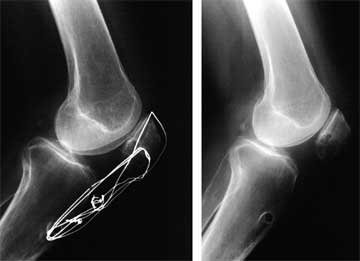

For those rare cases where patellar tendon lengthening is indicated, the procedure is done at this point. If possible, the patient’s patellar tendon undergoes a z-plasty lengthening and then is augmented with a graft made from the patient’s semitendinosus and gracilis tendons.

In the worst cases, the patellar tendon is essentially non-existent and a second graft (usually an allograft) must be used along with the STG to create a new tendon. These major operative procedures require at least 6 months of rehabilitation to obtain the best recovery possible.